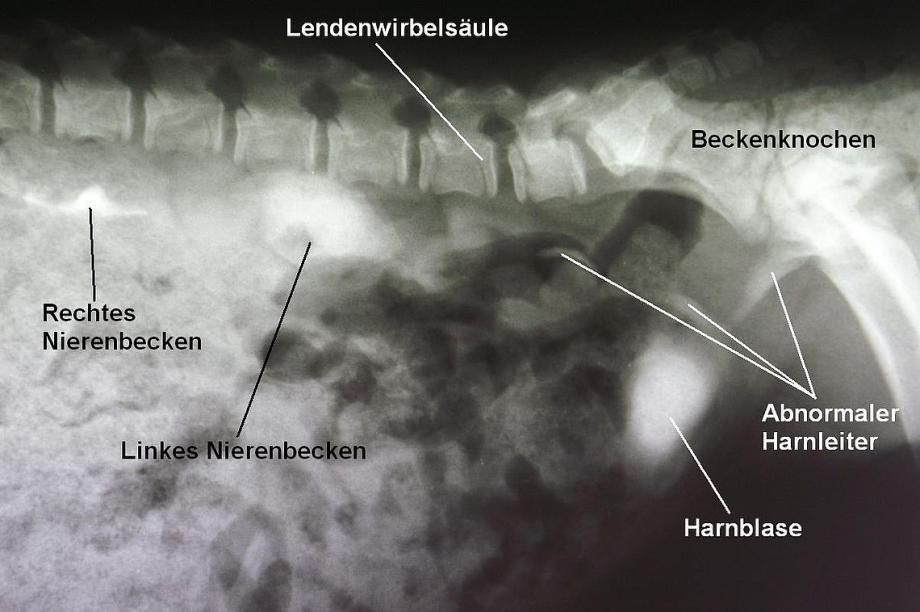

Zur genaueren Abklärung des Verdachts wird ein sogenanntes IVP (intravenöses Pyelogramm) angefertigt. Hierzu wird dem Hund intravenös ein Kontrastmittel injiziert, welches über die Nieren ausgeschieden wird und so auf einer Röntgenaufnahme die Nieren, die Harnleiter (Ureter) und die Blase verstärkt darstellt. In einem "normalen" Röntgen sind die zu untersuchenden Harnleiter nicht erkennbar.

Bei "Gipsy" wird ersichtlich, dass das linke Nierenbecken und der linke Ureter stark erweitert sind. Das rechte Nierenbecken erscheint normal, der rechte Ureter leicht erweitert. Zudem kann gezeigt werden, dass mindestens ein Harnleiter nicht wie normal in die Blase, sondern weiter hinten in die Harnröhre mündet. Die Harnblase füllt sich ebenfalls mit Kontrastmittel, was dafür spricht, dass zumindest ein Teil des Urins normal in die Blase gelangt.